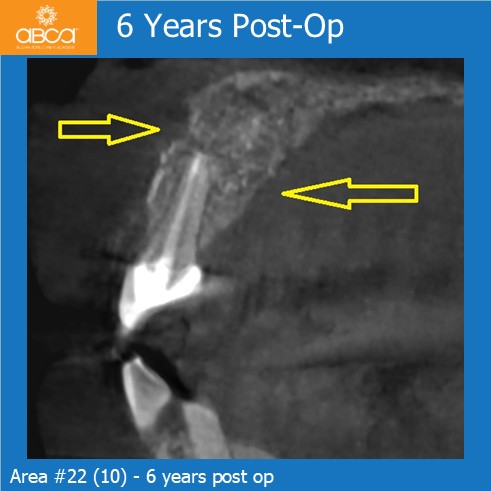

At the six-year follow-up, we observed good bone remodeling and healing, including complete and stable regeneration of both cortical plates.